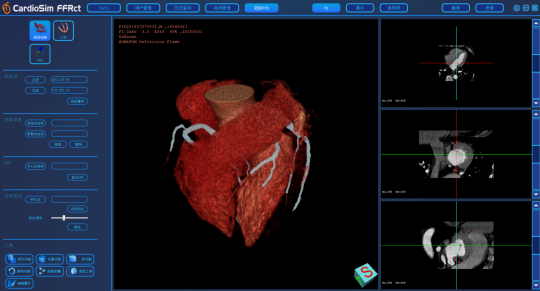

产品简介:

我司CardioSim FFR 产品,基于冠状动脉CT影像定量计算获得冠状动脉FFR,预期供培训合格的医疗技术人员用于成人患者冠状动脉病变血管的功能学评价。临床中还应结合患者的临床病史、症状、其他诊断结果和临床医生的专业判断来综合评价冠状动脉血管。软件核心包扩冠脉中心线提取,心肌重构以及FFR计算。针对造影剂不足的冠脉,如果重构出现分支断裂,可以进行修复连接。同时,包含对冠脉点云的切割等多种功能,确保在FFR计算之前,冠脉的形态学能得到的还原。